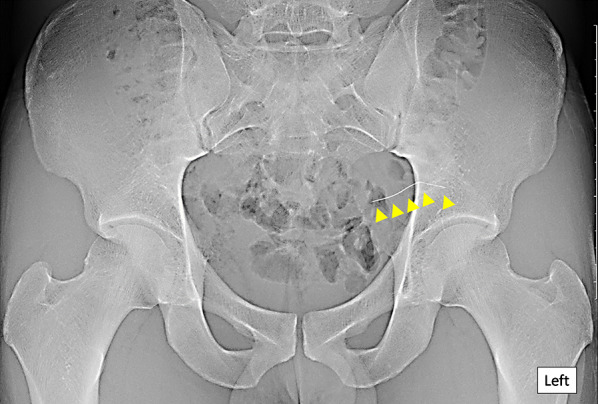

Fig. 1.

Abdominal X-ray examination on admission. A thin, 40-mm-long, metallic foreign body resembling an acupuncture needle is seen